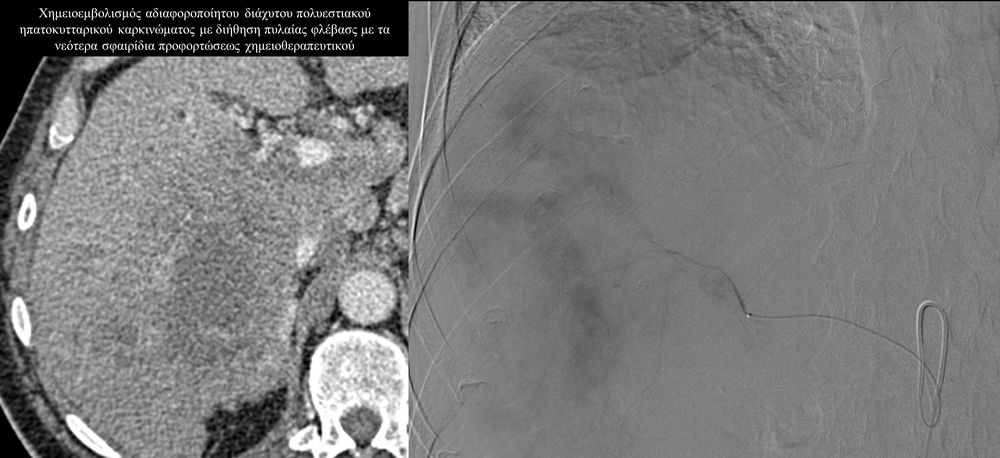

Ο χημειοεμβολισμός έχει καθιερωθεί σαν θεραπεία εκλογής στο ενδιάμεσο στάδιο του ηπατοκυτταρικού καρκινώματος.